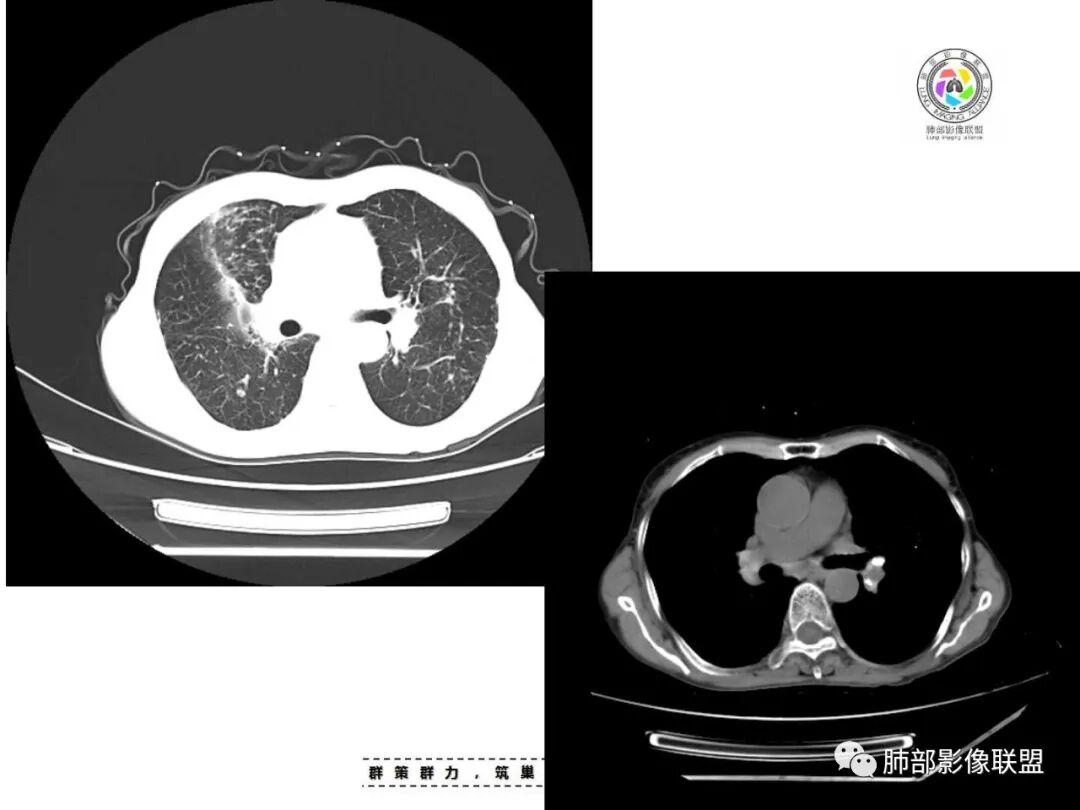

*小结节,直径2-5mm,边缘清楚或不清楚,小叶中心性和胸膜下。

*弥漫分布,以上叶和后部为主,

*融合团块,形态不规则,含坏死区。

*局灶性小叶中心性肺气肿。

*不规则型或瘢痕型肺气肿。

*淋巴结肿大和钙化。

1.胸膜下为主,簇状分布,大小不等,新旧不等,树芽,密度偏高等等都结核病变影像学特点。

2.多数尘肺结节影相对比较随机,没有胸膜下分布优势。

尘肺结节显得“游离”、清晰,一般较为均匀,很少呈多形性、斑片、树芽或新旧不等改变,晚期形成的纤维块状影多是双上肺中带对称分布,也很少纵隔偏移。

2.能够完全将尘肺排除在外吗(如II期)?不能!左肺内中带较均匀分布的较均匀是具有尘肺影像学特征而不支持结核血播的。此外双肺门及纵隔淋巴结钙化也更多见于尘肺,尤其是矽肺。